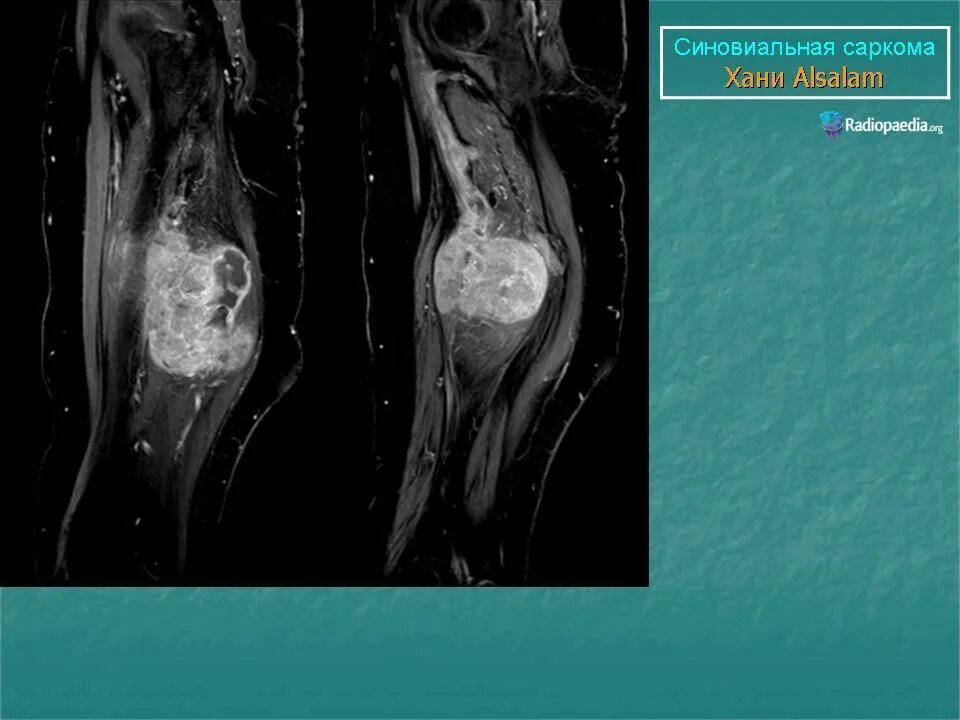

Саркома мрт